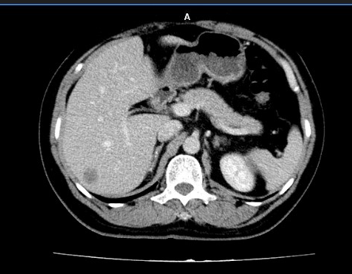

* Trường hợp số 1: bệnh nhân Nguyễn Đức H, nam, 51 tuổi, được chẩn đoán ung thư trực tràng di căn gan. Kết quả sinh thiết khối u trực tràng là ung thư biểu mô tuyến, không có đột biến gen KRAS hay BRAF, cũng như không bộc lộ gen dMMR. Thông qua hội chẩn đa chuyên khoa, bệnh nhân được hóa trị tiền phẫu theo phác đồ hóa chất kết hợp điều trị đích CapeOX + Bevacizumab và đánh giá lại sau 5 chu kỳ. Kết quả cho thấy bệnh nhân đáp ứng tốt với điều trị, thể hiện trên nội soi (hình 1), cắt lớp vi tính (hình 2) và cộng hưởng từ, khối u giảm kích thước, tổn thương gan khu trú tại hạ phân thùy 6 kích thước 34 mm (đánh giá giai đoạn u là cT4N2M1 trước điều trị hóa chất và ycT4N0M1 sau điều trị hóa chất). Bệnh nhân đã được tiến hành phẫu thuật nội soi hoàn toàn cắt trực tràng, và toàn bộ mạc treo trực tràng qua đường hậu môn (Transanal Total Mesorectal Excision - TaTME) (Hình 3) (được thực hiện bởi kíp Phẫu thuật Ống tiêu hóa) kèm cắt u gan hạ phân thùy 6 (được thực hiện bởi kíp Phẫu thuật Gan mật). Hậu phẫu bệnh nhân ổn định, phục hồi nhanh, ra viện sau mổ 7 ngày.

Hình 2: hình ảnh di căn gan từ ung thư trực tràng